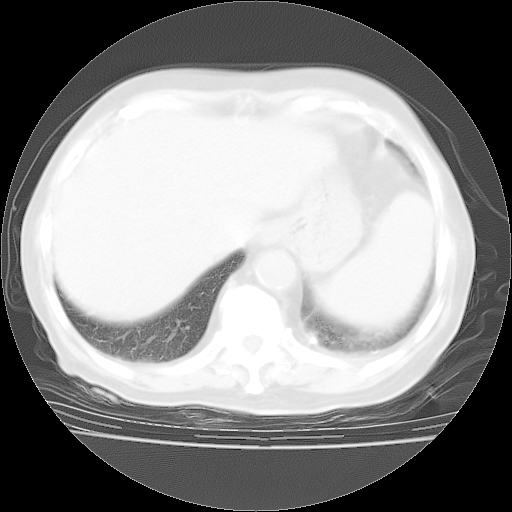

4月28日肺部CT